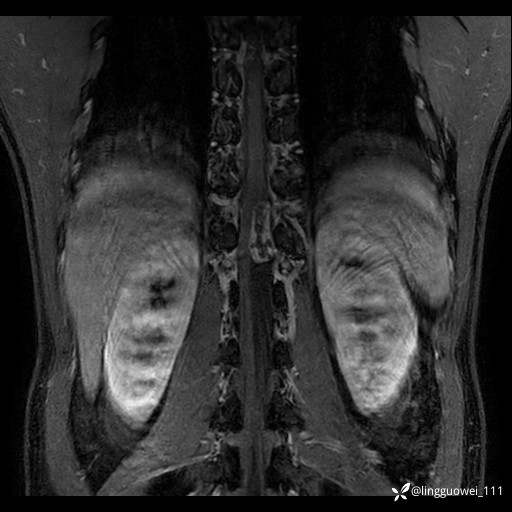

男,38岁,反复腰痛伴双腹股沟区痹痛半年,加重1月。

腰椎MR,注意脊髓异常信号,与伪影鉴别,一不小心就会漏诊

T2WI T2WI+FS